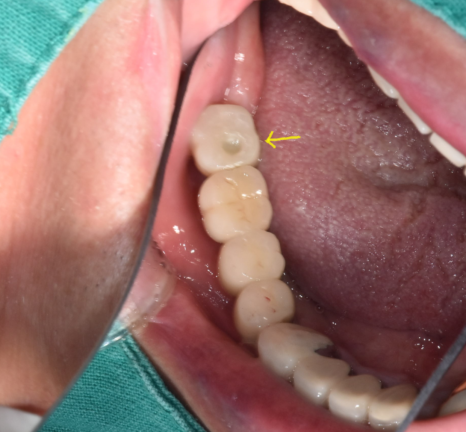

입안에 전체적으로 보철을 한 상태입니다.

치료를 안한 치아는 한개도 없는 상황이죠~

검사를 해보니...

기존 신경치료를 한 치아에 문제가 있어보였는데요.

230607

입에서 냄새가 나는 이유는 많지만

신경치료 한 치아 뿌리 끝 부분으로 뼈가 녹아있고

염증 소견이 확인됩니다.

총 4군데에서 문제가 있었지만

가장 안좋은 부분은 오른쪽 위아래

이 부분들은 흔들리고 있었습니다.